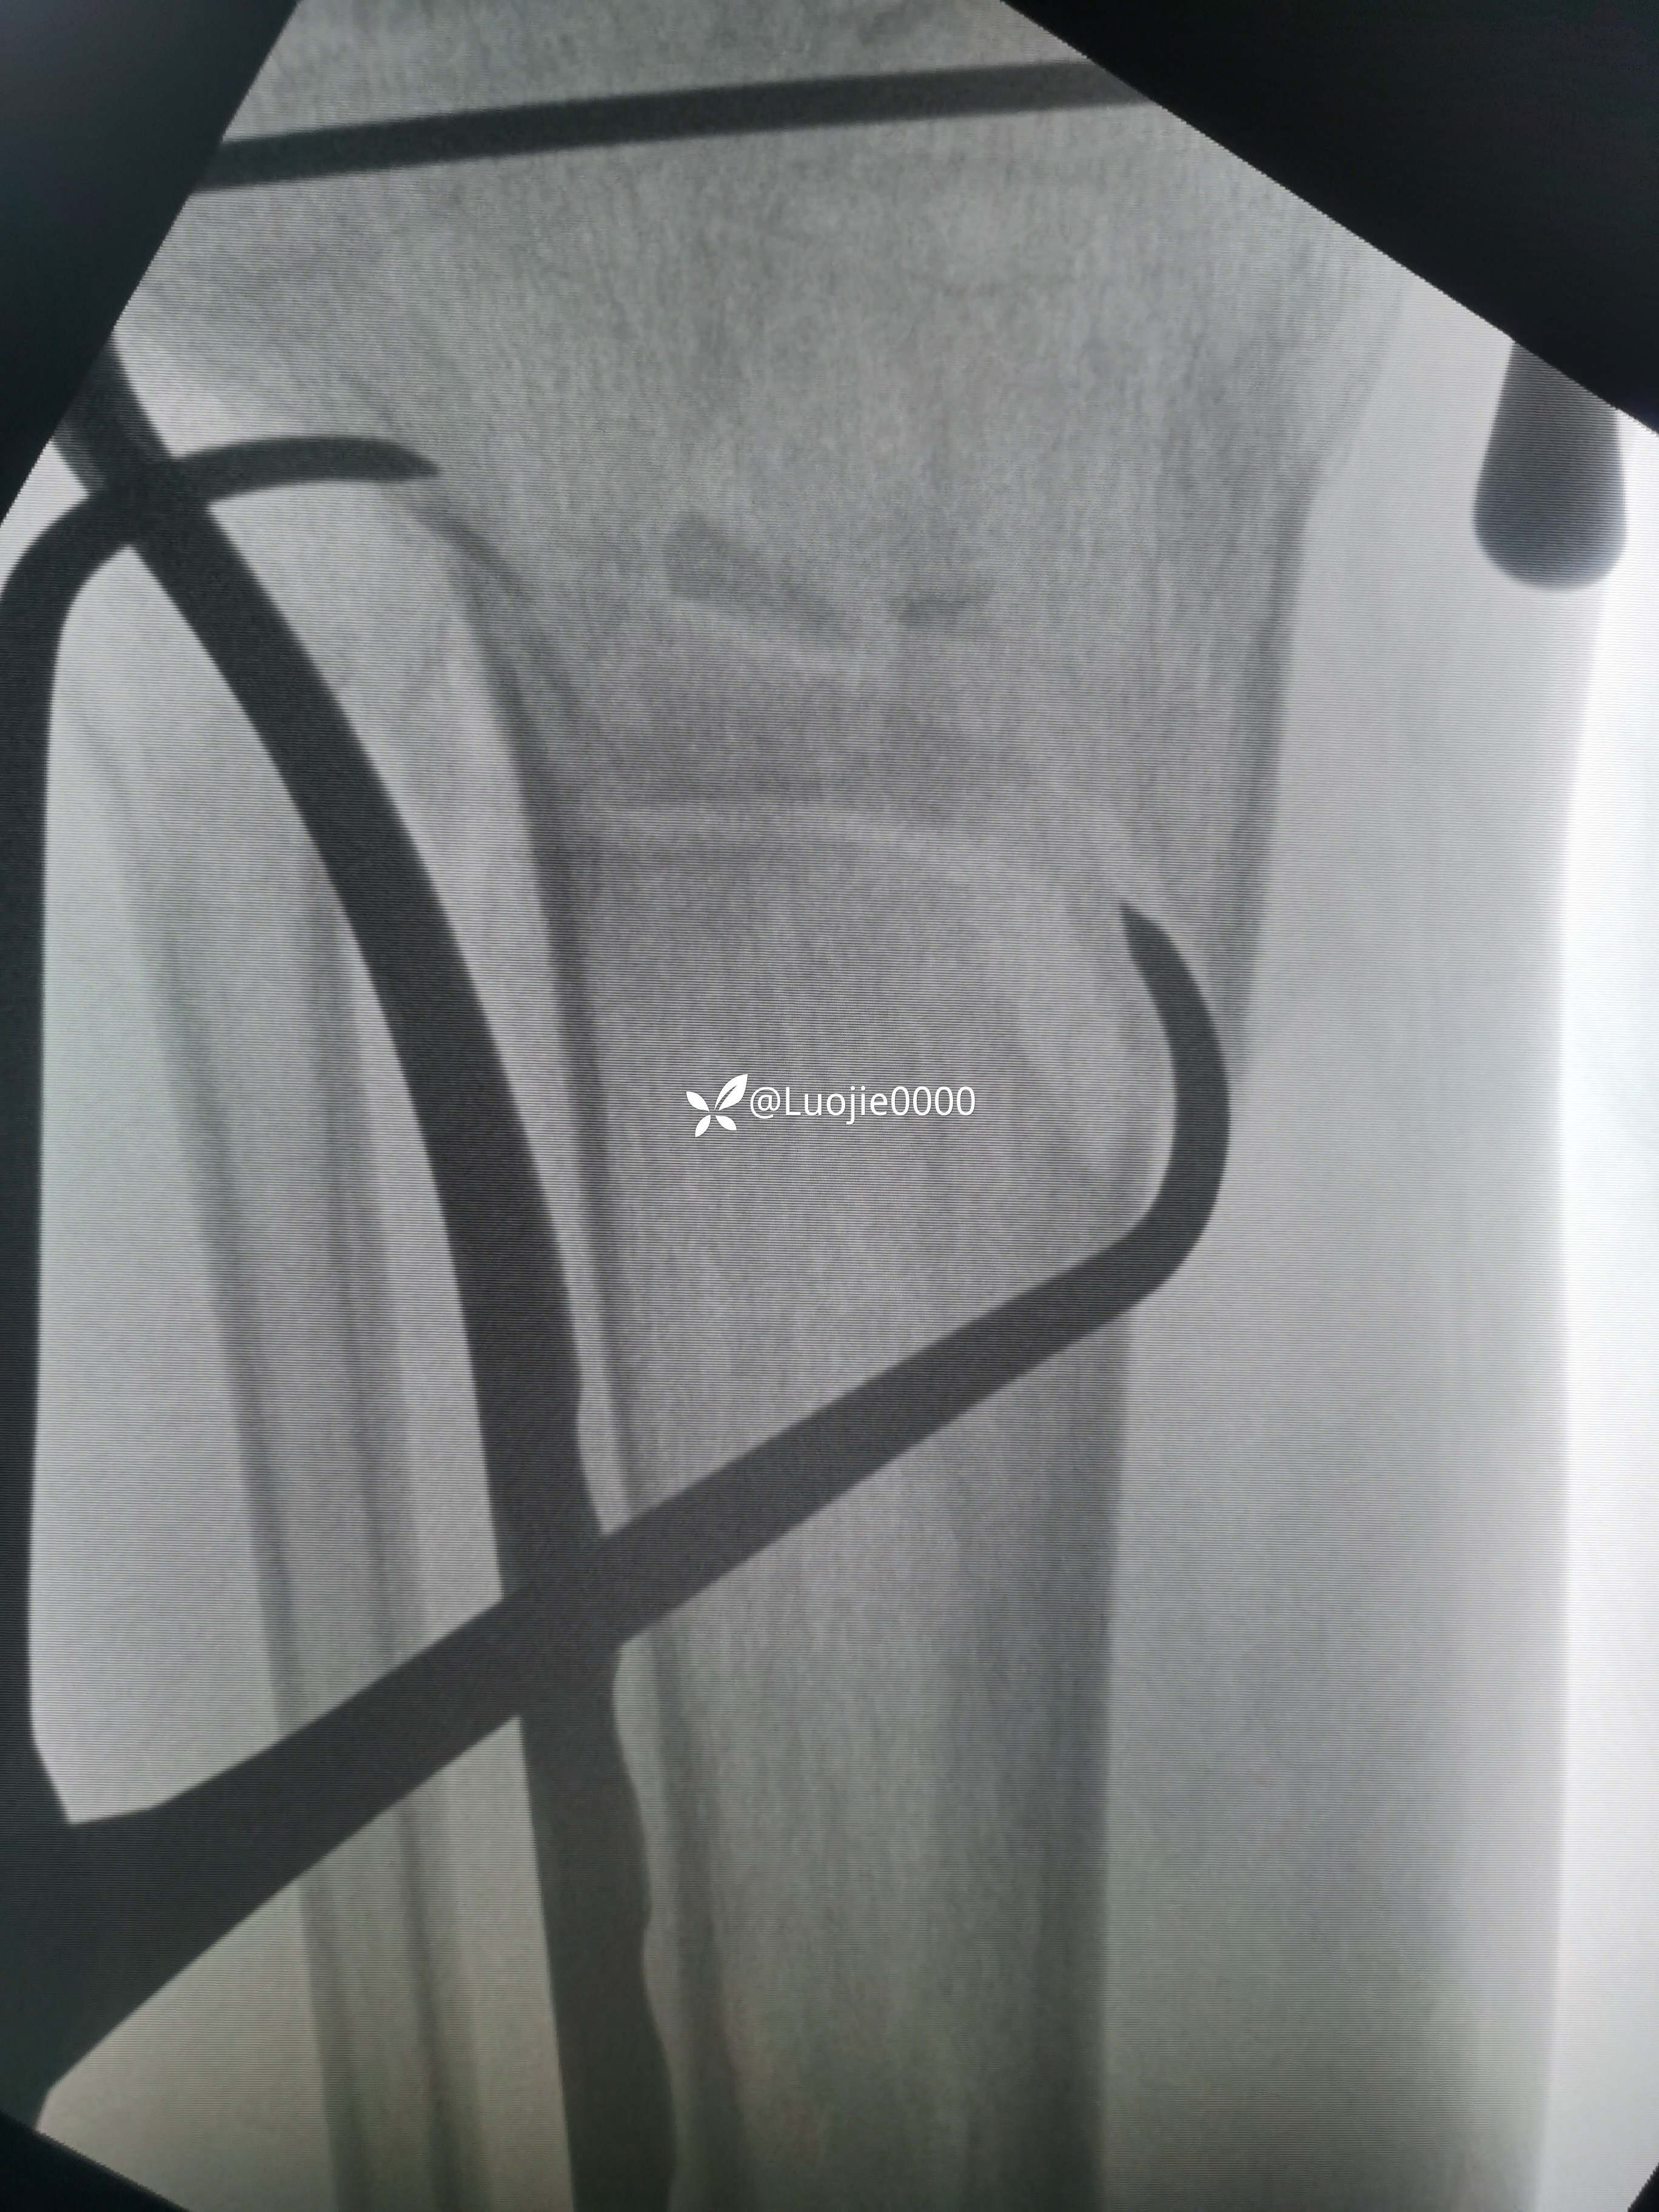

辅助检查:DR及CT提示:左胫骨近端及腓骨头骨折。

影像资料如下: